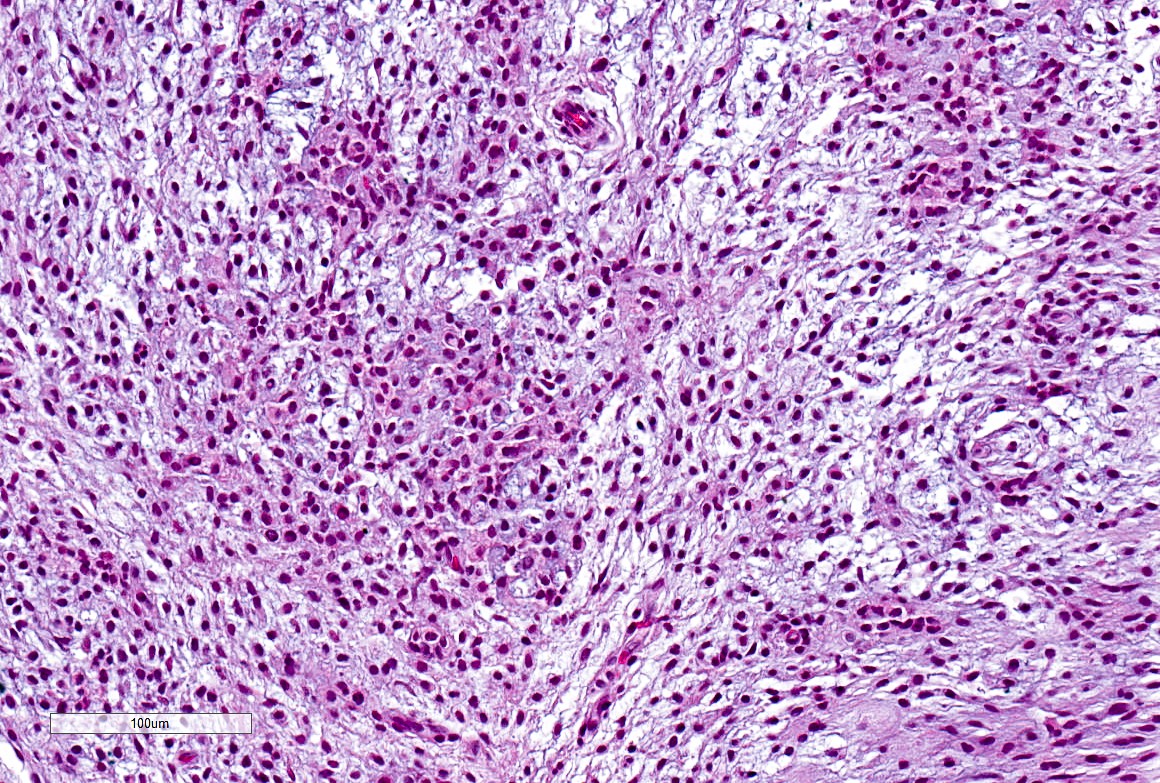

Microscopic (histologic) description

- Well demarcated tumor, often entrapped within skeletal muscle and frequently multilobulated (Am J Surg Pathol 2018;42:1297, Head Neck Pathol 2015;9:315)

- Stromal background may be hyalinized or demonstrate mucoid, myxoid or chondromyxoid areas

- Cords, strands or sheets of oval, round, fusiform or polygonal bland cells, sometimes arranged in a reticular / net-like or globoid pattern (Am J Surg Pathol 2018;42:1297)

- Myxoglobulosis-like changes have been noted (Virchows Arch 2003;442:302)

- May focally demonstrate fine calcifications, cellular atypia, necrosis, multinucleated giant cells (Am J Surg Pathol 2018;42:1297, Head Neck Pathol 2015;9:315, Oral Surg Oral Med Oral Pathol Oral Radiol Endod 1996;82:417)

- Cystic, slit-like spaces or hemorrhagic areas often noted (Head Neck Pathol 2014;8:329)

- Mitotic figures not seen (Head Neck Pathol 2015;9:315)

Microscopic (histologic) images